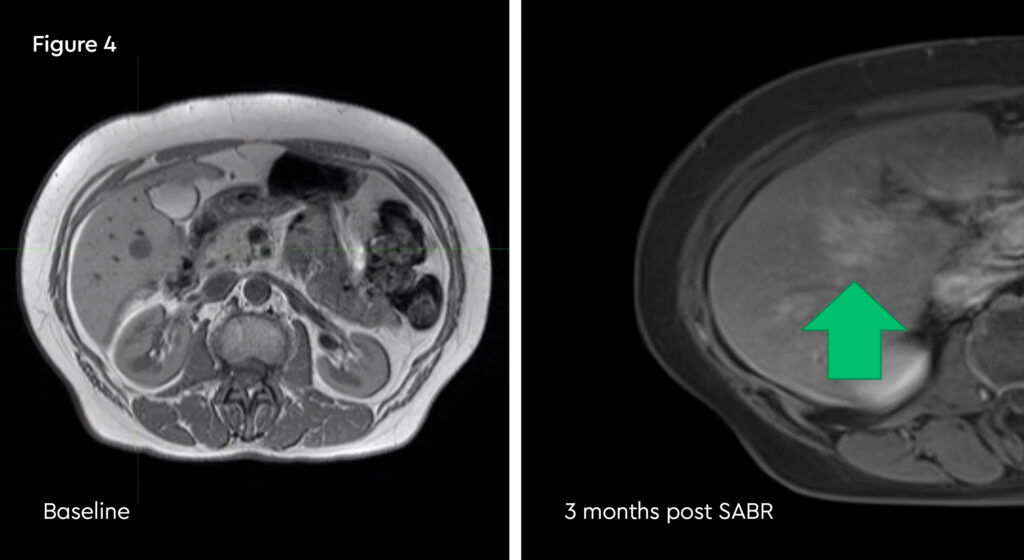

Multiple liver metastases

A case study of MRI-guided radiotherapy to treat multiple liver metastases

A 64-year-old lady with a history of HER2 negative ER+ breast cancer. She initially presented with stage pT2N1M0 disease and had previously undergone wide local excision and post-op radiotherapy, chemotherapy and endocrine therapy. She relapsed with three liver metastases on FDG PET and MRI and on the basis of the SABR COMET trial results, and a preference to avoid surgery, was referred for stereotactic ablative radiotherapy (SABR).

The challenge here was the number of metastases. Two of them were in a position not amenable to percutaneous radiofrequency ablation, and given that breast cancer can recur in other tissues as well as liver, surgery was likely not to be the optimal approach. The lesions were positioned in different segments of the liver, making it challenging to treat with conventional SABR due to the need for an internal target volume (ITV), leading to an increased mean liver radiation dose and therefore potentially reduced dose to the tumours.

The patient accepted treatment on the MR linac despite being apprehensive about the treatment time. The lesions were readily visible on the MRIdian planning scans with IV liver-specific contrast (figure 1). She completed treatment as planned, and we were able to deliver 50 Gy in five fractions to all three lesions. During the adaptive replanning process we could see that the gross tumour volumes (GTVs) were decreasing in size as SABR proceeded. She has also continued with second line endocrine therapy.

Fig 1: Pre-treatment MRIdian planning scans showing three small, scattered liver metastases

The patient did develop some rib tenderness related to radiation dose to the most peripheral lesion, but this settled with simple analgesia and time. MRI scan at three months showed the tumours were almost completely clear and a further scan at six months showed no active cancer. The patient requires ongoing endocrine therapy to control her disease.

Fig 4: Post-treatment MRI scan, showing a well demarcated ablation zone

The improved soft tissue definition, beam gating and adaptive replanning made possible by MRIdian allowed an entirely non-invasive approach to ablating this lady’s liver metastases. MRI-guidance added value through greater confidence in delineating and tracking gross tumour volumes smaller treatment margins and maximising the ablative radiation dose.